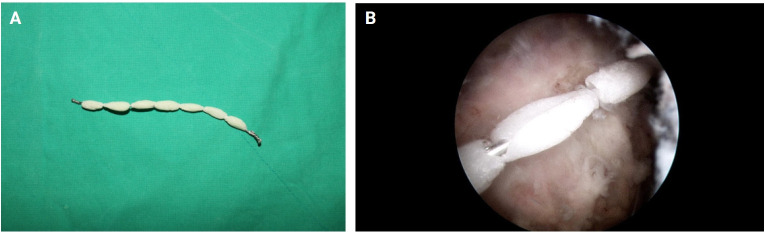

Background: This study sought to evaluate the effectiveness of a combined treatment approach for septic shoulder arthritis involving arthroscopic synovectomy and use of antibiotic-impregnated polymethylmethacrylate (PMMA) beads for localized antibiotic delivery.

Methods: This retrospective study included 22 patients with septic shoulder arthritis treated at our institution between 2017 and 2023. The treatment involved arthroscopic lavage, debridement, and insertion of antibiotic-impregnated PMMA beads. Patients were evaluated preoperatively and postoperatively based on laboratory tests, imaging, joint fluid analysis, and physical examination. Treatment efficacy was assessed based on normalization of C-reactive protein (CRP) levels, pain reduction as measured using a visual analog scale (VAS), and improvement in shoulder function according to Constant-Murley score.